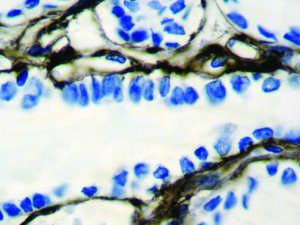

This activation induces inflammatory monocytes to highly express IL-6, starting a localized and then systemic cascade effect that results in hyperproduction of IL-6, which accelerates the inflammatory process. Because IL-6 also increases vascular permeability, excessive levels cause blood vessels to become very leaky. This, along with clotting factors released from vascular endothelial cells, stimulates the coagulation cascade, resulting in microthrombosis (tiny clots), which leads to ischemia and tissue death of the kidney, intestines, heart, liver, brain and extremities.